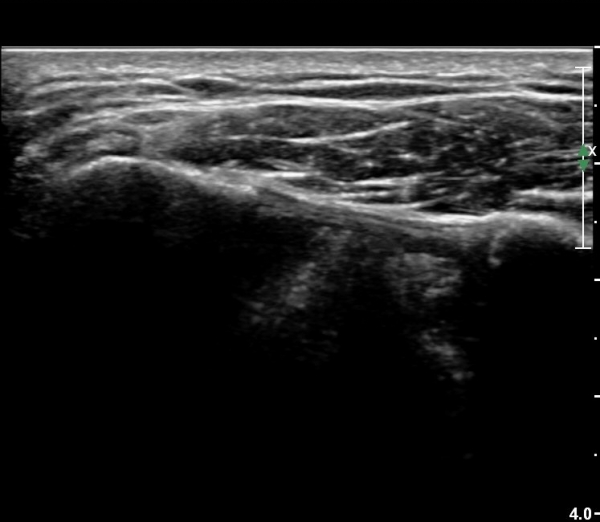

¾î±ú¸¦ ³»Àü, ³»È¸ÀüÇÑ »óÅ¿¡¼­ ±Ø»ó°ÇÁ¾´Ü¸é°Ë»ç»ó  ³»ÃøºÎ ÆÄ¿­ÀÌ °üÂûµÇ°í»çÁø 6, 7)

Ⱦ´Ü¸é°Ë»ç¿¡¼­ ±Ø»ó°Ç ³»ÃøºÎ ÆÄ¿­°ú ºÎÁ¾ÀÌ °üÂûµÈ´Ù(»çÁø 8), ŽÃËÀÚ¸¦ ¸»´ÜÀ¸·Î À̵¿ÇÏ´Ï

±Ø»ó°Ç ºÎÂøºÎ ÆÄ¿­ÀÌ ¶Ñ·ÈÇÏ´Ù(»çÁø 9).